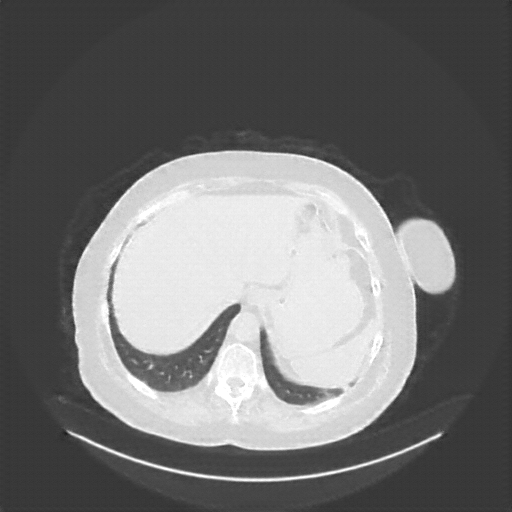

Reconstructed NATIVE CT scan (cycle consistency)

Lung window (WL -600, WW 1500 β†’ Low βˆ’1350, High +150)

Mediastinum window (WL 40, WW 400 β†’ Low βˆ’160, High +240)